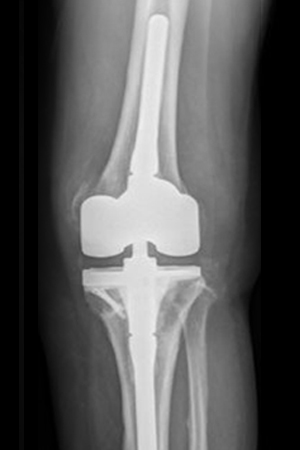

인공관절 재치환술은 성공적인 인공관절 치환술 후 5년 이내, 10년 이상으로 크게 나눠집니다. 수술 후 2~3년 이내 감염이나 사고가 일어날 시 재수술을 하게 되며 수술 후 10년 이상 되었다면 인공관절이 닳고 많이 써서 불안정성이 생기고 염증이 생겨 인공관절 재치환술을 시행하게 됩니다. 인공관절 재치환술은 무릎 불안정성, 골절, 염증 등과 내과적 질환 문제도 발생되어 고난도 수술 기술을 요구하므로 인공관절 재치환술 경험이 풍부한 숙련된 전문의에 한해 시행될 수 있습니다.

인공관절 재치환술은 할까? 말까? 하며 정하는 수술이 아닙니다. 인공관절 치환술을 받은 환자가 어쩔 수 없는 사고, 골절, 인대 파열, 감염 등의 이유로 자신의 몸에 있는 인공관절에 무리가 발생하면 일상생활을 할 수 없기 때문에 선택의 여지없이 재수술을 받아야 합니다.

SNU서울병원의 ‘인공관절’은 한자 성별 맞춤형 인공관절로 남,여 각 환자의 고유한 해부학적 구조 차이를 설계 및 보완한 인공관절입니다. 기존 인공관절과는 차별화되어 좌/우 구별된 디자인으로 여러 사이즈를 보유하고 있으며 해부학적, 기능적으로도 우월합니다.

인공관절 재치환술은 수술시간도 인공관절수술보다 오래 걸리며 환자의 체력적 소모도 큽니다. 때문에 수술 전, 수술 중, 수술 후에 고려해야 할 사항이 많고 만성질환을 앓는 환자분들도 대다수이므로 무엇보다 의료진들과의 협진 시스템도 중요한 사항입니다. SNU서울병원은 정형외과 외에도 신경외과, 마취통증의학과, 가정의학과, 영상의학과 등 전문의의 협진 시스템이 체계적으로 구축되어 환자의 상태에 즉각 대응이 가능합니다.

세계최초! 환자의 뼈 크기와 남/녀 뼈의 모양을 해부학적 환자 맞춤으로 2mm 간격의 좌/우/Standard/Narrow 각각 12개 사이즈로 총 48개 환자맞춤 사이즈를 보유하여 수준 높은 정밀함을 선보입니다.

최대155도 까지 관절 굴곡으로 좌식생활에 적합한 한국형 인공관절로서 커버력 UP!